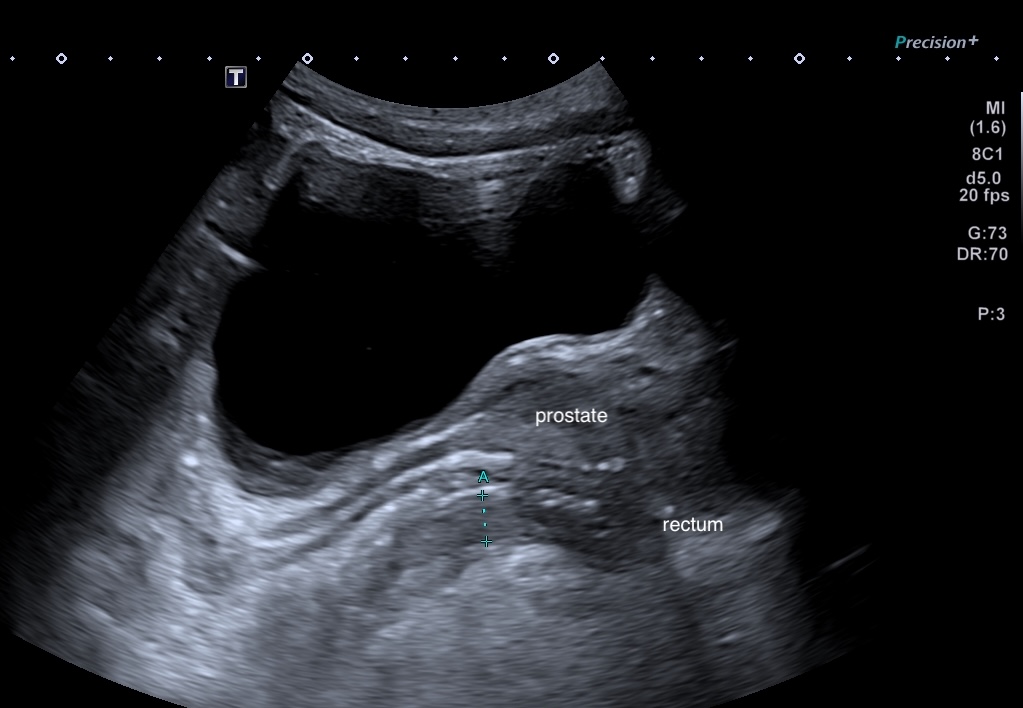

l'axe prostate-vésicule séminales

Le rectum

Maladie de Crohn, rectum (épaissisement asymétrique prédominant à la partie postérieure) coupe passant par la prostate